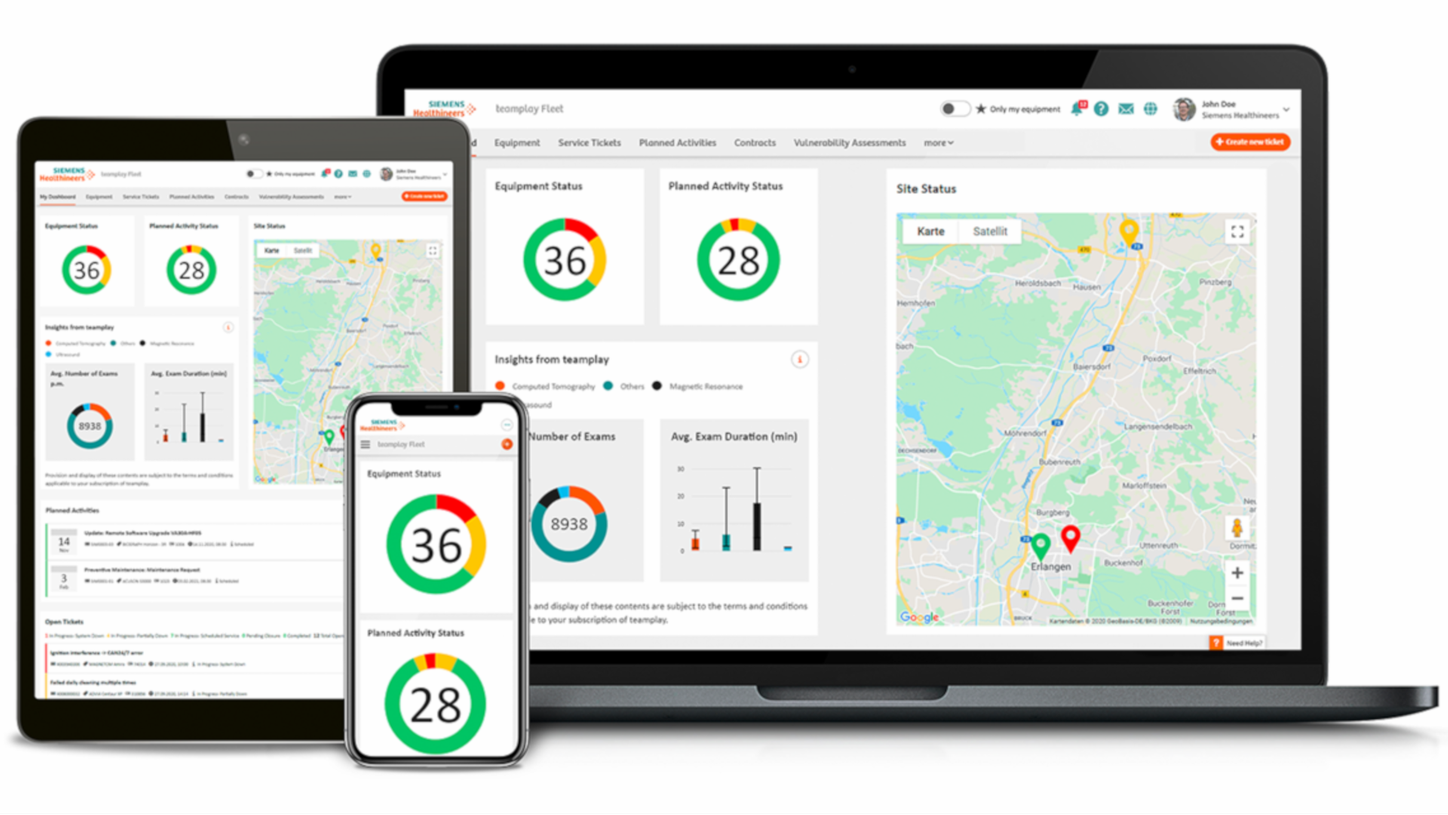

The ACUSON Sequoia is an advanced diagnostic tool that integrates cutting-edge technology and AI-powered applications to streamline diagnostic processes. This system is designed to cater to patient-specific needs, ensuring accuracy and efficiency in various clinical settings such as Radiology, OB/GYN, Shared Service and beyond.

ACUSON Sequoia’s new advanced features are designed to improve diagnostic confidence and workflow across a wide range of clinical settings.